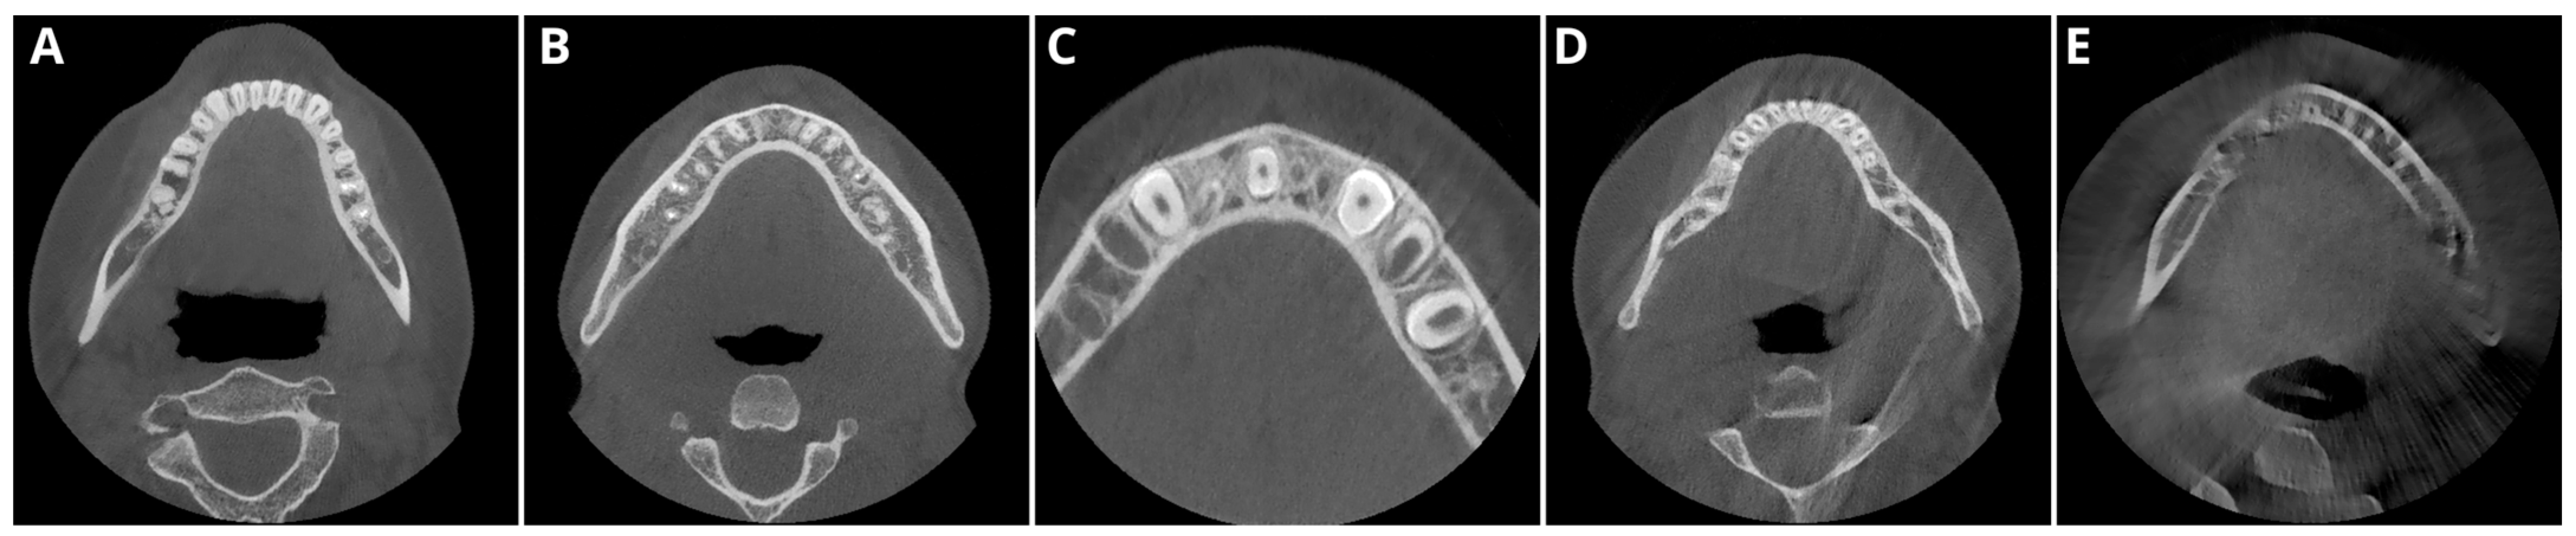

2.2. Image Acquisition and Postprocessing

2.3. Objective Image Quality

- Periapical region of tooth 15 within the maxillary bone,

- Periapical region of tooth 33 within the mandible,

- The spongious bone of the mandible in the mental foramen area,

- Muscles of the tongue.